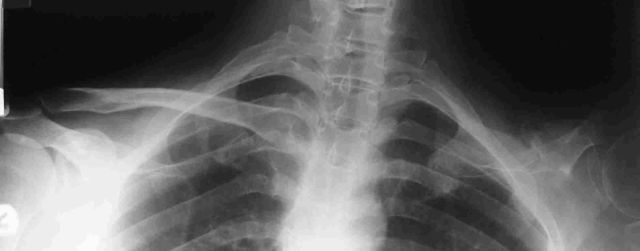

Before the operation the right hand side clavicle can be clearly seen on this x-ray, and below that the post-operative x-ray clearly shows the titanium implant.